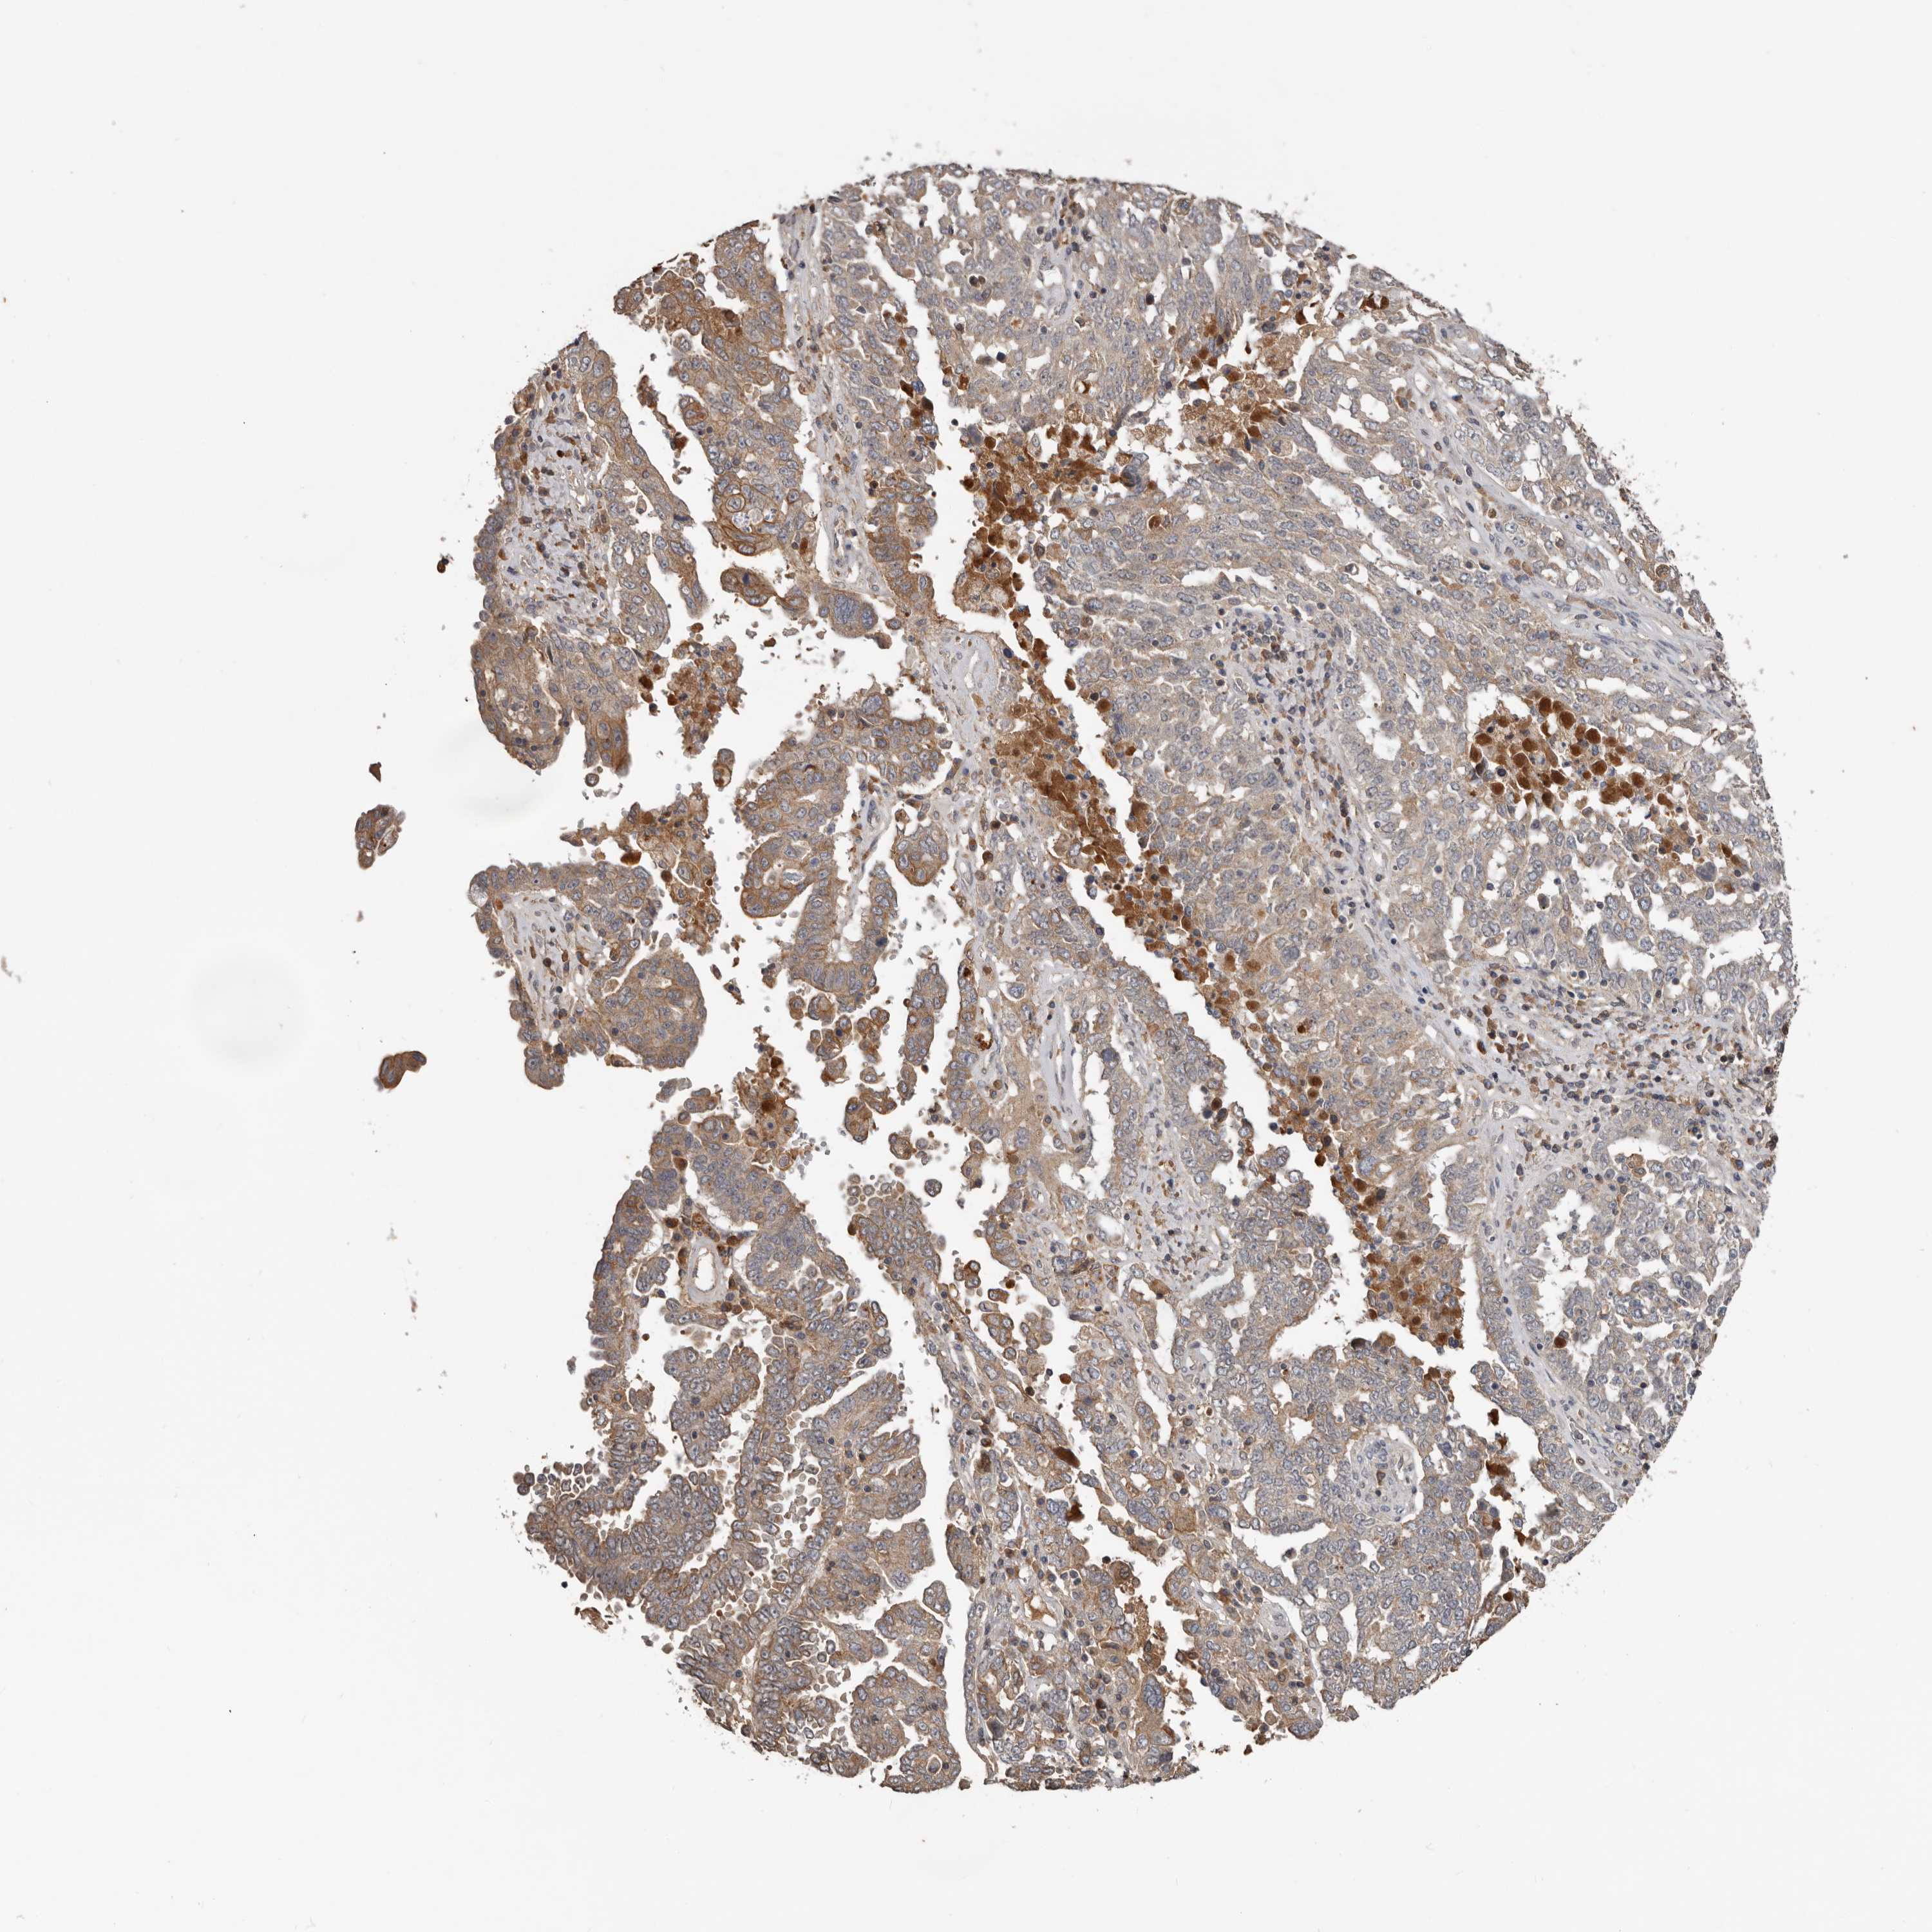

OVARIAN CANCER - Protein expressioni

A mouse-over function shows sample information and annotation data. Click on an image to view it in a full screen mode. Samples can be filtered based on level of antibody staining by selecting one or several of the following categories: high, medium, low and not detected. The assay and annotation is described here.

Note that samples used for immunohistochemistry by the Human Protein Atlas do not correspond to samples in the TCGA dataset.

Antibody stainingi

Antibody staining in the annotated cell types in the current human tissue is reported as not detected, low, medium, or high, based on conventional immunohistochemistry profiling in selected tissues. This score is based on the combination of the staining intensity and fraction of stained cells.

Each image is clickable and will lead to virtual microscopy that enables deeper exploration of all samples and also displays staining intensity scores, fraction scores and subcellular localization as well as patient and tissue information for each sample.

Antibody HPA027895

Staining

High

Medium

Low

Not detected

Intensity

Strong

Moderate

Weak

Negative

Quantity

>75%

75%-25%

<25%

None

Location

Nuclear

Cytoplasmic/membranous

Cytoplasmic/membranous,nuclear

Cystadenocarcinoma, serous, NOS

Carcinoma, endometroid

Cystadenocarcinoma, mucinous, NOS

Carcinoma, NOS